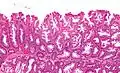

Low magnification micrograph of an SSL.

Low magnification micrograph of an SSL. -

SSLs are diagnosed by their microscopic appearance; histomorphologically, they are characterized by (1) basal dilation of the crypts, (2) basal crypt serration, (3) crypts that run horizontal to the basement membrane (horizontal crypts), and (4) crypt branching. The most common of these features is basal dilation of the crypts.

Unlike conventional colonic adenomas (e.g. tubular adenoma, villous adenoma), they do not (typically) have nuclear changes (nuclear hyperchromatism, nuclear crowding, elliptical/cigar-shaped nuclei).